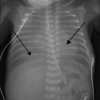

What would you see on CXR in respiratory distress syndrome?

Ground glass appearance

Discuss the management of respiratory distress syndrome; include antenatal management and management of premature neonate

_Antenatal management_ * Antenatal steroids (e.g. dexamethasone) to mothers with suspected or confirmed preterm labour *(increase production of surfactant)* _Premature neonate management_ * Endotracheal surfactant * CPAP *(to help keep lungs inflated whilst breathing)* * Oxygen *(aim sats 91-95%)* * Intubation & ventilation (if severe) Support with breathing can be gradually stepped down as baby improves.